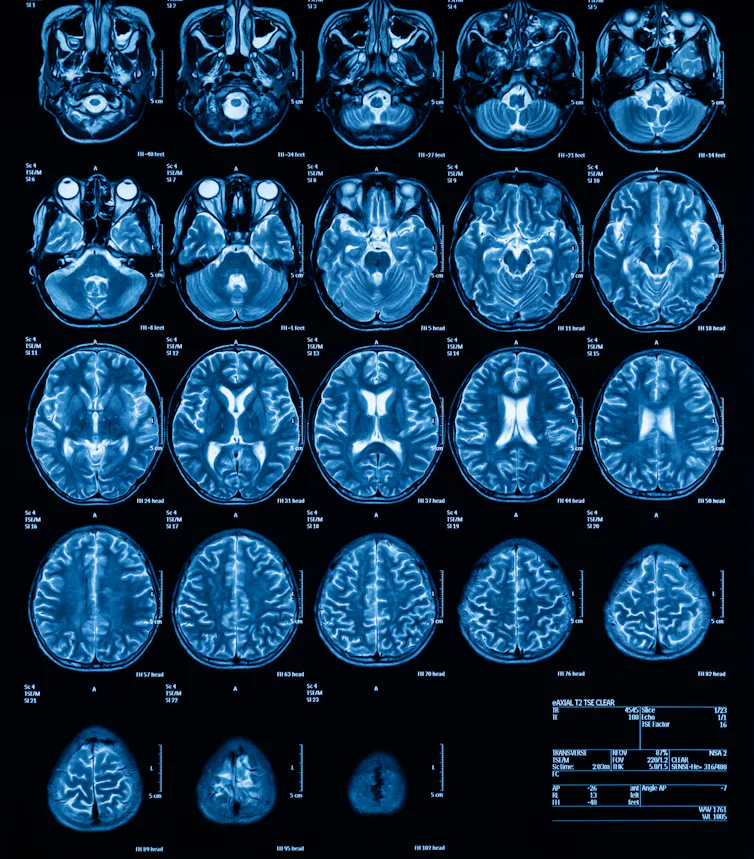

Blindsight results from damage to an area of the brain called the primary visual cortex. This is one of the areas, as you might have guessed, responsible for vision. Damage to primary visual cortex can result in blindness – sometimes total, sometimes partial.

So how does blindsight work? The eyes receive light and convert it into information that is then passed into the brain. This information then travels through a series of pathways through the brain to eventually end up at the primary visual cortex. For people with blindsight, this area is damaged and cannot properly process the information, so the information never makes it to conscious awareness. But the information is still processed by other areas of the visual system that are intact, enabling people with blindsight to carry out the kind of tasks that we see in the case of Barry and Rick.